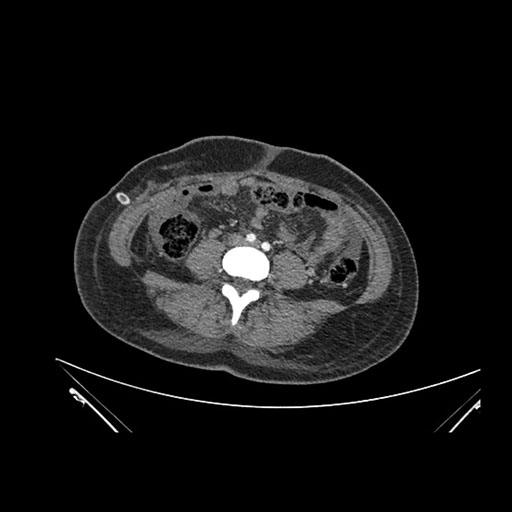

Imaging Analysis

Look through the patient's CT scan to identify any areas of concern for the necessary procedure.

Axial Arterial

Based on initial findings, which issue(s) would you be most concerned about?